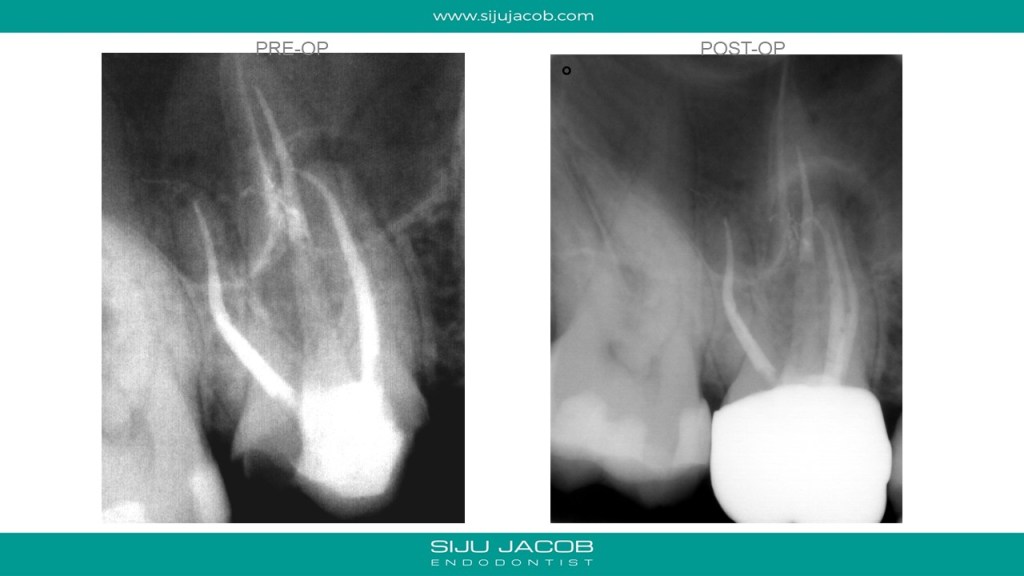

Re-treatment due to missed Mb2 is probably the most commonly referred procedure that I do. And almost every time, I leave the other canals alone. in this case, the referral did endo and placed a new crown, after which the patient had pain followed by a sinus tract. G.p cone tracing of the sinus tract led to the mesial root. We managed to do this with the very conservative opening, thereby preserving the new crown. (in hindsight, i probably should have left the mb1 alone)